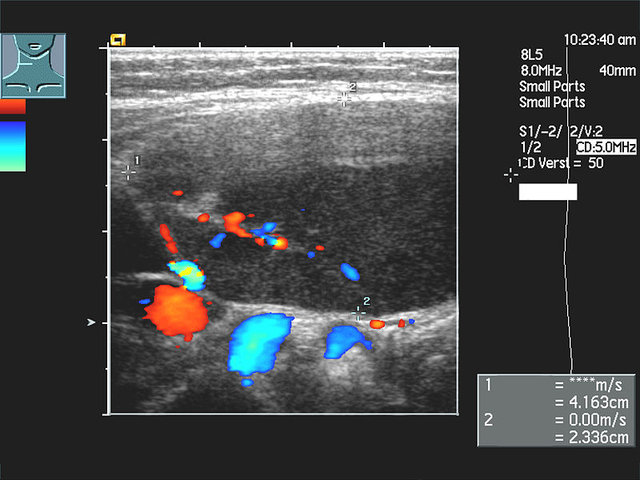

Sonographie des Halses bei hochmalignem Non-Hodgkin-Lymphom der Halslymphknoten (Transversalschnitt mit farbkodierter Duplexsonographie) © wikipedia.de/Christaras A, CC BY 2.5